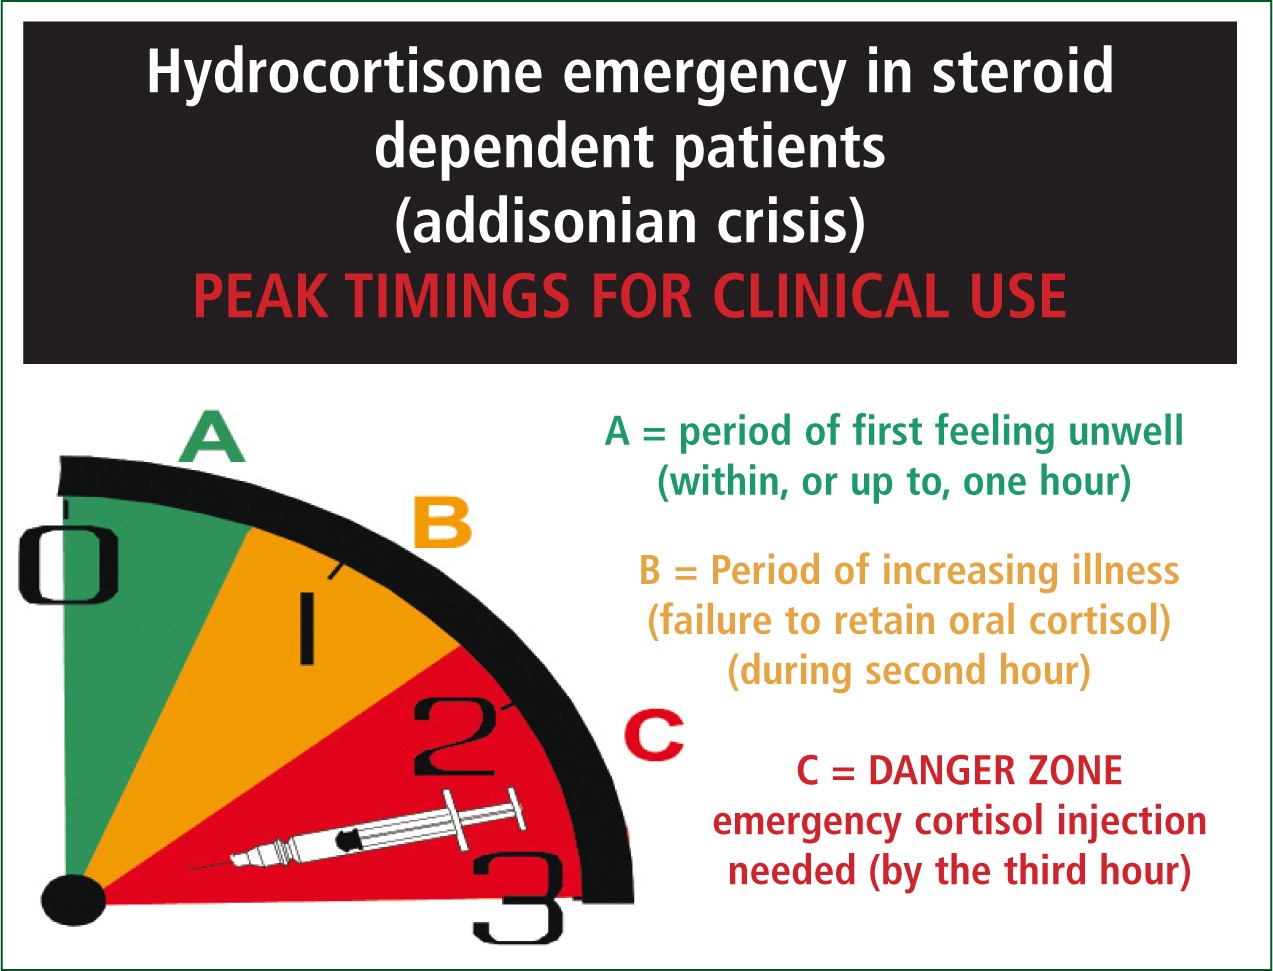

When Your Body Runs on Empty: Understanding Low Cortisol After Immunotherapy

When Fitness Changes Overnight: Living and Exercising with Immune-Related Adrenal Insufficiency

Living with not just cancer but “adrenal insufficiency” thrown in for fun.

Immunotherapy and Adrenal Insufficiency: When Treatment Saves You… But Changes You